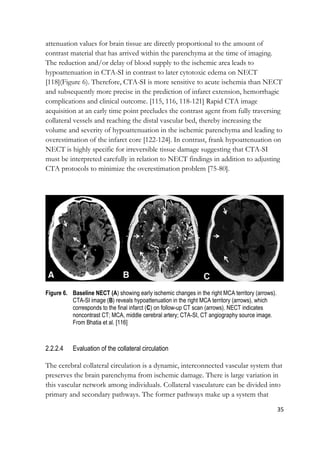

attenuation values for brain tissue are directly proportional to the amount of

contrast material that has arrived within the parenchyma at the time of imaging.

The reduction and/or delay of blood supply to the ischemic area leads to

hypoattenuation in CTA-SI in contrast to later cytotoxic edema on NECT

[118](Figure 6). Therefore, CTA-SI is more sensitive to acute ischemia than NECT

and subsequently more precise in the prediction of infarct extension, hemorrhagic

complications and clinical outcome. [115, 116, 118-121] Rapid CTA image

acquisition at an early time point precludes the contrast agent from fully traversing

collateral vessels and reaching the distal vascular bed, thereby increasing the

volume and severity of hypoattenuation in the ischemic parenchyma and leading to

overestimation of the infarct core [122-124]. In contrast, frank hypoattenuation on

NECT is highly specific for irreversible tissue damage suggesting that CTA-SI

must be interpreted carefully in relation to NECT findings in addition to adjusting

CTA protocols to minimize the overestimation problem [75-80].

Figure 6. Baseline NECT (A) showing early ischemic changes in the right MCA territory (arrows).

CTA-SI image (B) reveals hypoattenuation in the right MCA territory (arrows), which

corresponds to the final infarct (C) on follow-up CT scan (arrows). NECT indicates

noncontrast CT; MCA, middle cerebral artery; CTA-SI, CT angiography source image.

From Bhatia et al. [116]